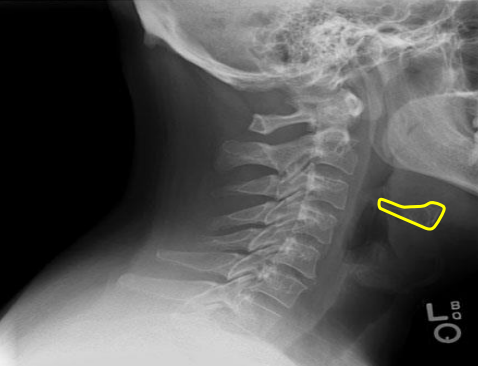

Mandible

Hyoid bone

Mitchel marker